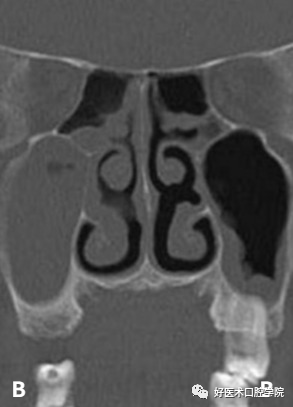

A:上颌窦粘液囊肿(周围可见骨质破坏) B:上颌窦积液(周围无骨质破坏)

也称作是黏膜囊肿,粘膜下囊肿等,是一种良性浆液性囊肿,是上颌窦黏膜中的浆液性腺体的导管开口阻塞,导致管腔上皮的囊性扩张所致,X线检查可见具有明显圆形边缘的阻射圆顶形结构,体积较小,大小不一,常见圆形、椭圆形、半球形,数量不确定,可以是一个,也可以是多个,常见于上颌窦窦口处。

常见上颌窦底部,局部黏膜充血外渗膨胀,由于液体潴留在结缔组织而产生,呈微小的半球形或椭圆形,均匀而且不透明,CBCT和根尖周片显现明显,表现为上颌窦底的穹窿形,未被上皮包绕固称为假性囊肿,多被认为是牙源性感染导致,多可见因牙周病或根尖周病破坏的牙槽骨。

关于上颌窦潴留囊肿和假性囊肿的术语和分布,文献上存在很大的混淆,它们经常以圆顶状阴影聚集在上颌窦底上,影像上对于两者很难判断。